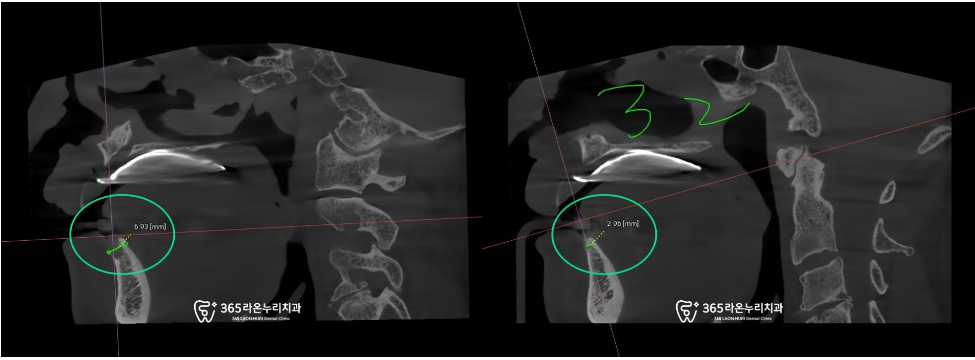

수술 전 CT를 촬영해 치조골의 두께를

확인합니다. 보통 남촌동 치과 에서

이렇게 확인한 데이터를 바탕으로

픽스처의 사이즈가 결정됩니다.

남촌동 치과 의 이번 케이스는

치조골이 많이 얇기 때문에

기다리는 기간을 충분히 가져야 됩니다.